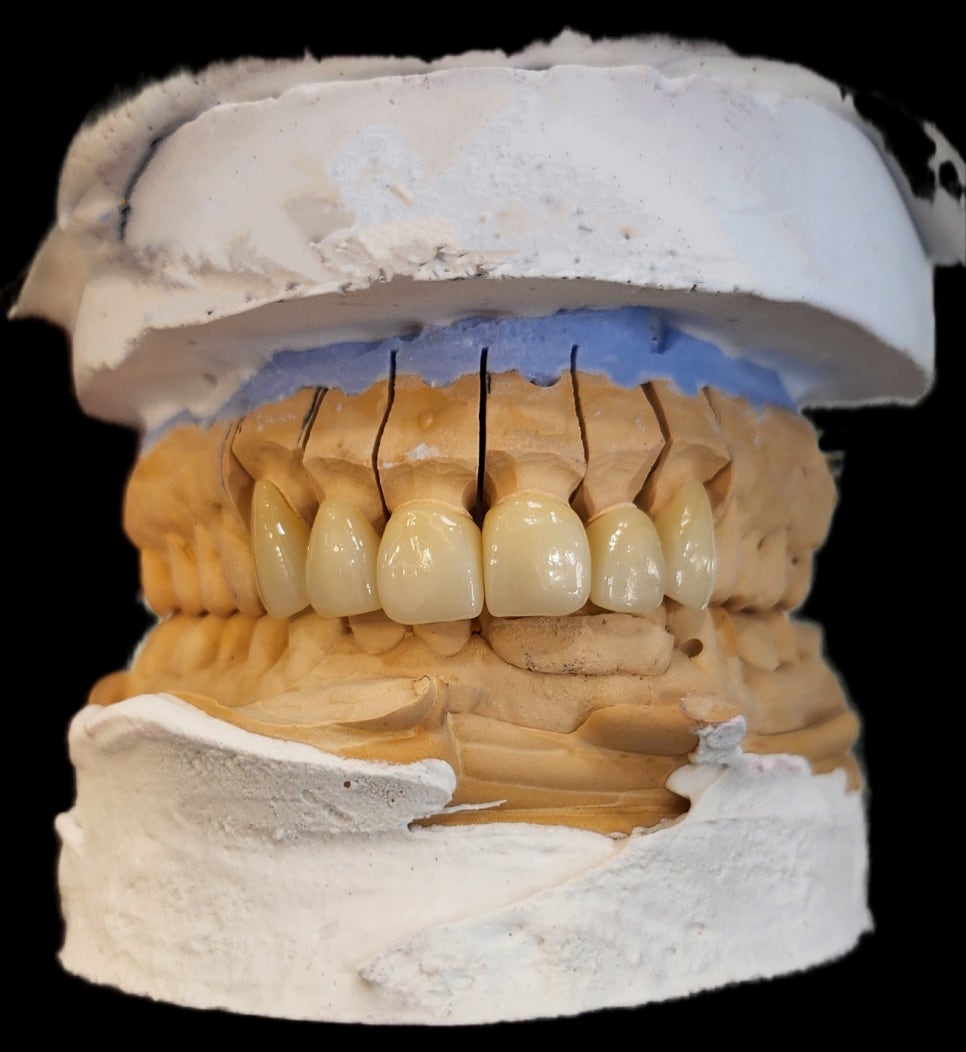

앞니 쪽 심미치료를 하기 위해서는 기공소와의 협업이 가장 중요하다고 생각합니다.

우선적으로 치아의 삭제량을 결정하기 위해

기공소에 의뢰하여 치아의 형태 디자인 제작을 의뢰합니다.

이 케이스에서 진단 모형이 꼭 필요한 이유는 치아의 돌출 정도가 다르기 때문에

치아를 삭제하기 위한 기준이 필요하기 때문입니다.

최종 보철물이 제작되어 적용이 되어있는 모델 상입니다

중간에 임시치아 제작 과정에서 애를 좀 먹었지만

저를 믿고 기다려주신 환자분께

최종 보철물은 아주 예쁘게 제작을 해드리기로 약속했습니다.